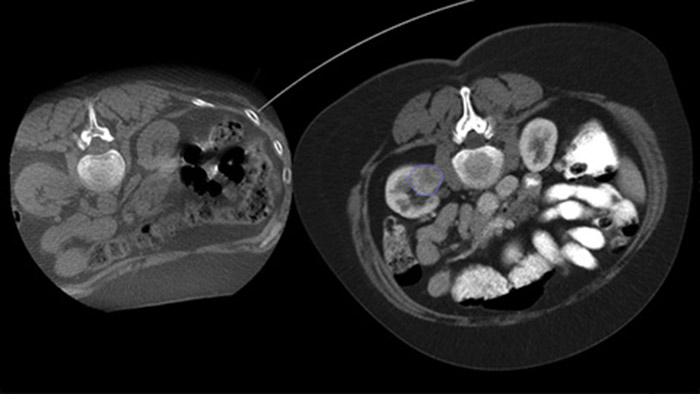

Dual View permite la superposición de una imagen 3D previa al procedimiento (TC/RM/TEP) sobre una THC Dual 3D intraprocedimiento para visualizar mejor las lesiones y acceder a información crítica para la planificación de la trayectoria de la aguja.